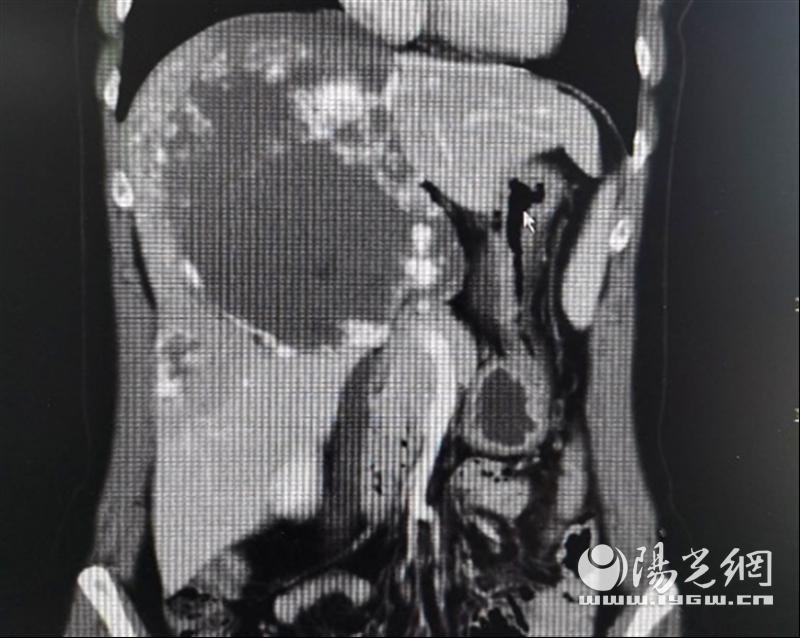

来自咸阳市的李女士,现年42岁,2个月前,她自觉上腹部疼痛,在当地医院检查后发现肝右叶有巨大占位性病变,疑为肝血管瘤。肝血管瘤是最常见的肝脏良性肿瘤,绝大多数患者并无症状,常常因为体检时查B超才发现。常见的肝血管瘤大多较小,直径超过10cm的就称之为巨大肝血管瘤,像李女士这样直径25cm大的则非常少见。

在慎重评估后,姚英民教授决定将李女士收住院,为其进行手术治疗。李女士入院后,肝胆外科姚英民教授、沙焕臣副教授对患者血管瘤病灶进行了精准术前评估。李女士所患血管瘤主要位于肝右叶、左内叶(IV段)及尾状叶,同时与第一肝门、第二肝门重要管道关系密切,推压变形,手术难度和风险非常之大。但手术治疗对患者非常有必要,这么大的血管瘤位于肝脏多条管道的纵横交错部,万一发生破裂,急诊处理会非常被动,很容易危及生命。